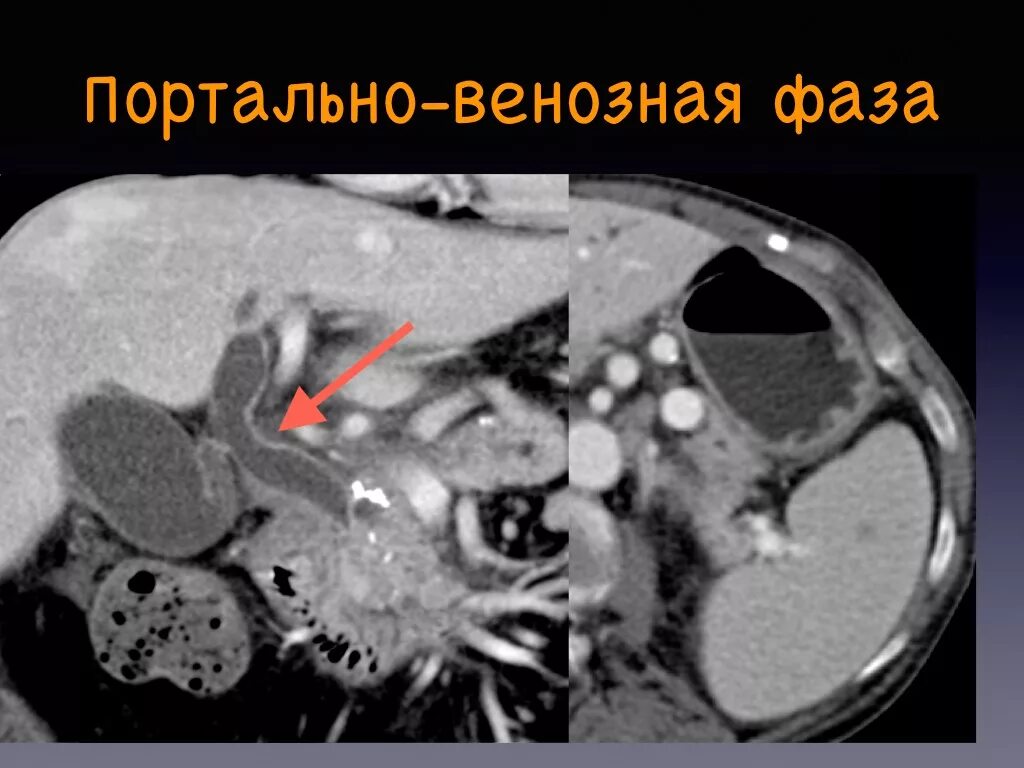

Фазы кт